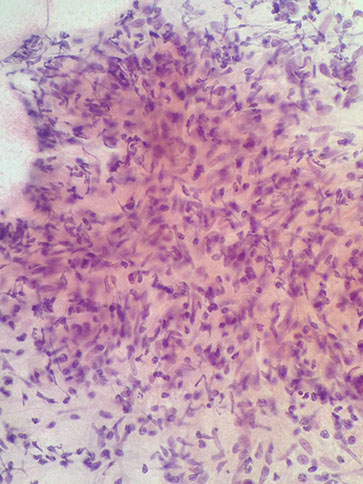

Ductal carcinoma

FNA biopsy yields disordered sheets, clusters and intact single cells

Nuclei are enlarged (2x RBC) and pleomorphic with hyperchromasia and fine to coarse chromatin

The cytoplasm is delicate and basophilic and may contain intracytplasmic lumens (sharply punched out cytoplasmic vacuole with thickened cytoplasmic rim, containing a dot of inspissated mucin)

The majority of breast cancers are ductal carcinoma.

The backround may contain cytoplasmic debri, ghost cells, necrosis or mucus